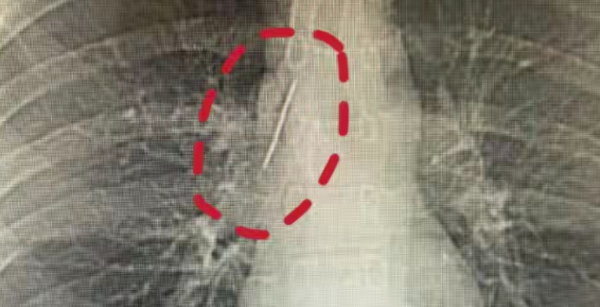

浙江嘉兴17岁小伙小陆参军体检时,意外发现胸腔内竟藏着一根5厘米长的锈迹缝衣针!这根针紧贴大血管、刺入肺组织,在他体内"潜伏"十余年,不仅没引发感染、气胸,日常运动也毫无异常,令医生直呼"医学奇迹"。

原来这根针大概率是小陆幼年时不慎误入体内,家人回忆他儿时曾有不明原因哭闹,或是意外发生时留下的隐患。医生紧急实施微创手术,成功将针完整取出。医生提醒,儿童体内异物潜藏风险极高,发现异常务必及时就医。